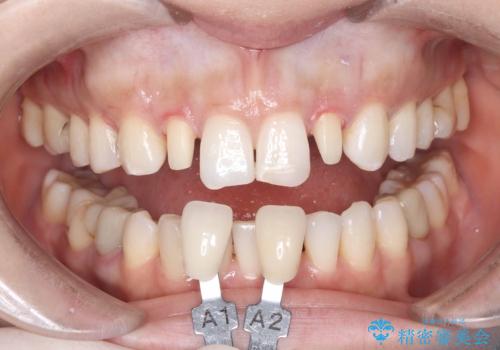

- 歯並びを矯正で整えたあと、上顎左右2番の歯(前歯の横の歯)の「矮小歯(歯が小さい状態)をオールセラミッククラウンで審美修復した症例です。

また、自然な色合いや形になるよう、歯科技工士と連携し、写真を撮影しながら細かく色合わせを行い、周囲の歯になじむよう丁寧に仕上げています。